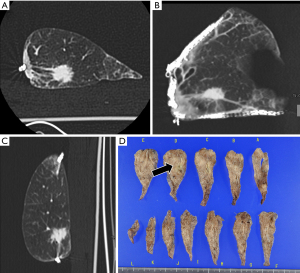

The resected specimens were inflated by the careful instillation of air. Puncture was performed at a distant site, where the pulmonary lesion was absent, using a 23-G puncture needle connected to an appropriately sized syringe. The instillation was done slowly in order to prevent alveolar wall destruction. The degree of inflation differs among specimens because air leak from the puncture site or stapled site eventually develops. After the specimen was placed in a plastic container, the specimen along with the container underwent conventional 64-detector CT (Revolution GSI; GE, Chicago, IL, USA) as soon as possible. The scan parameters were as follows: tube voltage, 80 kV; rotation time, 0.6 s; beam width, 20 mm; pitch, 1.375; slice thickness, 0.625 mm; slice interval, 0.625 mm; scan field of view (FOV), 8 cm; matrix, 512×512; recon type, HD Lung; noise index, 10. It generally takes 5 minutes or less for scanning of the resected specimen and image acquisition. The obtained images were evaluated intraoperatively in the operating room on multi-planner reconstruction images. Figures 1-3 show two representative cases with primary lung cancer.

One of the most important benefits of the present method is that we can measure the distance between the intrapulmonary lesions and any staple line (Figure 2) on multiplanar reconstruction images. This means that we can create multiple section images of the resected specimens without cutting the specimen itself, which can aid in determining how to make additional cut lines during performing additional resection for insufficient surgical margin.